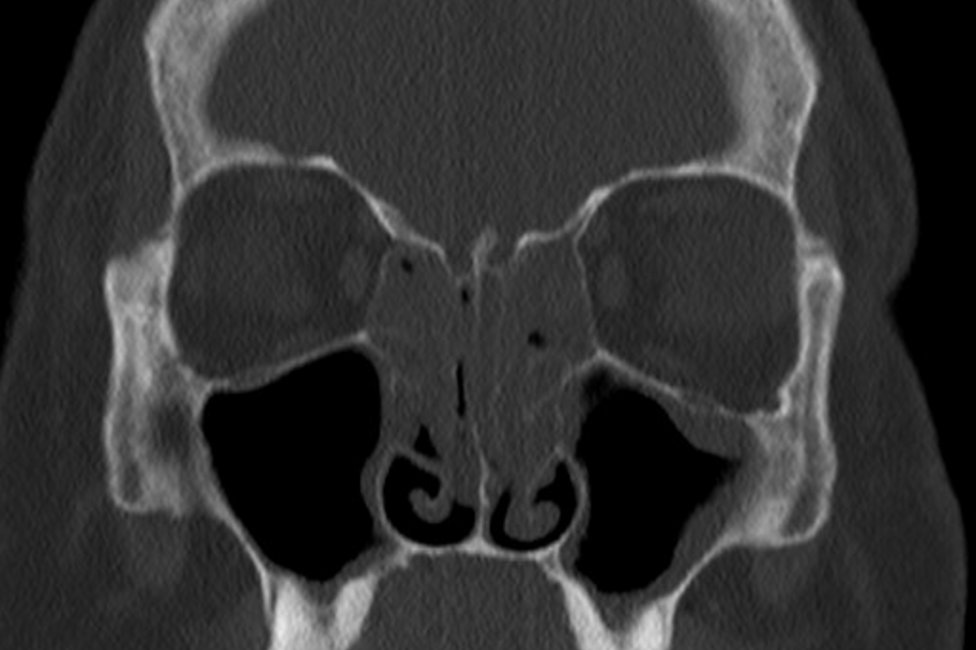

At the Department for Otorhinolaryngology 400 to 500 patients are diagnosed and (surgically) treated each week - amounting to tens of thousands of patients with various clinical pictures each year.